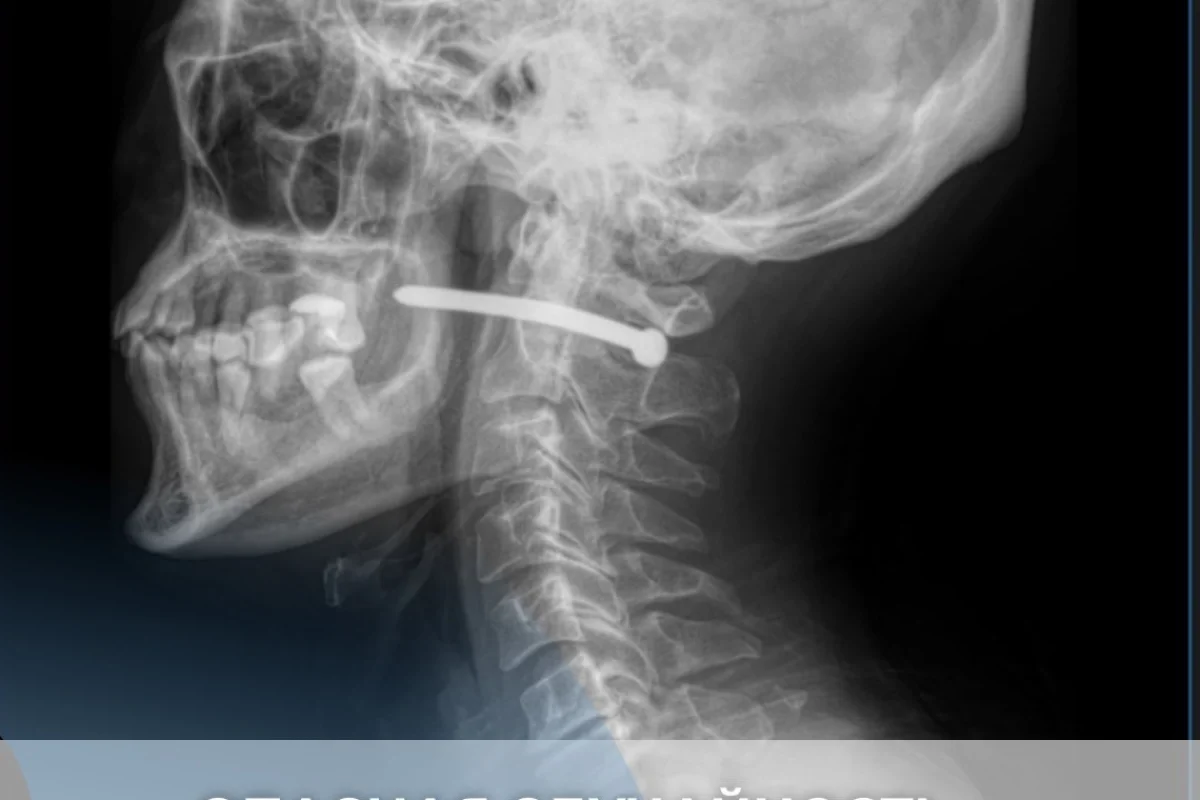

Во время ремонтных работ он по неосторожности получил травму гвоздём из пневматического пистолета. После рентген-исследования выяснилось, что гвоздь прошёл рядом с шейным отделом позвоночника.

«Мужчине чудом повезло — жизненно важные структуры не были задеты. Челюстно-лицевыми хирургами проведено удаление инородного тела, ревизия и обработка раны. После наложения швов и стерильной повязки пациент с рекомендациями отпущен домой», — сообщили в больнице.